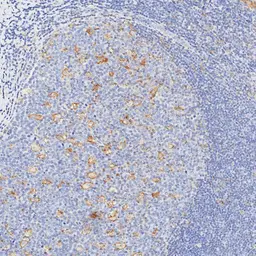

IHC-P analysis of human lymph node tissue using GTX639925 PD-L1 antibody [H302] HistoMAX™.

A subset of inflammatory cells stain PD-L1 positive.